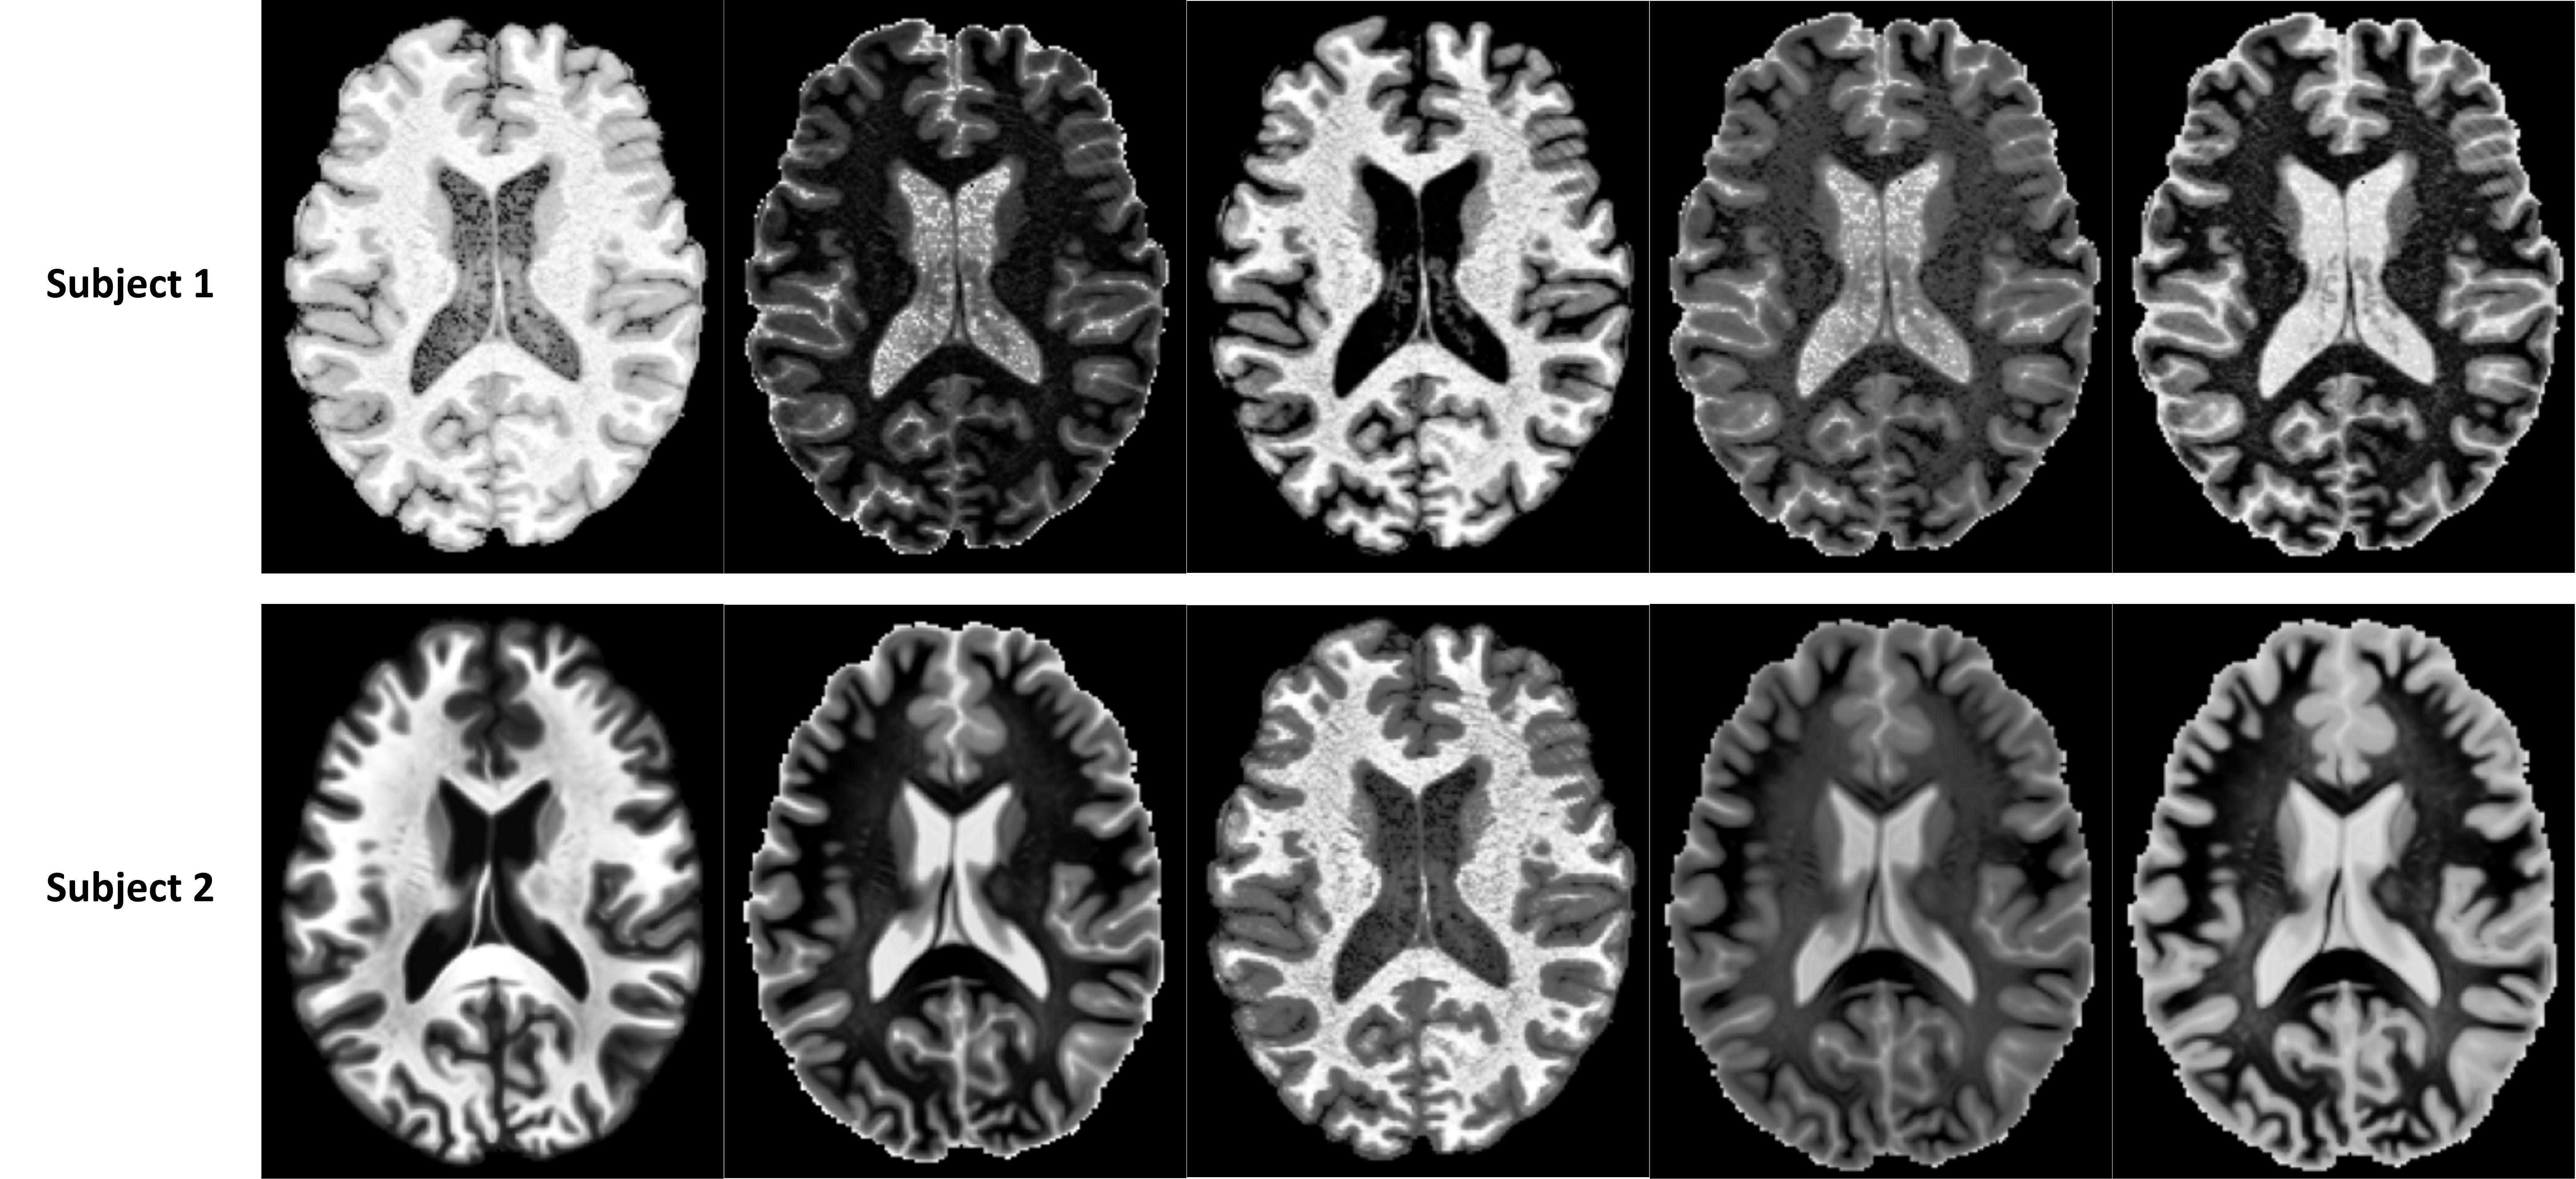

Training data: For the reference template (Itemplatesubscript𝐼templateI_{\text{template}}italic_I start_POSTSUBSCRIPT template end_POSTSUBSCRIPT), we used the widely adopted T1w ICBM152-MNI2009c Symmetric brain MRI template [18], along with 32 expert-annotated landmarks (𝑷𝑷\boldsymbol{P}bold_italic_P) based on the AFIDs protocol [53]. Although other brain landmark protocols also exist, we have chosen AFIDs due to its clinical significance and being the only public dataset of this kind. To train our model, we have curated multi-center datasets of balanced sexes and ages (18-90 yo) to build our training set. For our training set, we obtained 1544 brain MRI datasets (3T & 7T) by combining 581 T1w brain MRIs from the IXI dataset111https://brain-development.org/ixi-dataset, 105 7T T1w brain MRIs from the AHEAD dataset [2], 634 T1w brain MRIs from the HCP-A dataset [58], and 224 T1w brain MRIs from OpenNeuro [47, 52]. We conduct standard pre-processing for all scans: resizing and resampling to 193×229×193193229193193\times 229\times 193193 × 229 × 193 voxels and 1×1×11111\times 1\times 11 × 1 × 1 mm3𝑚superscript𝑚3mm^{3}italic_m italic_m start_POSTSUPERSCRIPT 3 end_POSTSUPERSCRIPT resolution, rescaling intensity values to [0, 1], skull-stripping using BEaST [15], applying an N4 bias field correction, and affine registration to the ICBM152 space [19].

Testing data: To evaluate the effectiveness of our method, we have utilized 122 scans from 4 different sources: 1) 30 T1w MRI scans from the HCP dataset [58] acquired on a 3T scanner, 2) 30 T1w MRI scans from the publicly available Open Access Series of Imaging Studies (OASIS-1) [33] database acquired on a 3T scanner, 3) 32 T1w MRI scans from the Stereotactic Neurosurgery (SNSX) dataset [53] acquired on a 7T scanner, and 4) 30 T2w MRI scans from the HCP dataset. For each scan, 32 AFIDs landmarks [53] were manually labeled by experts, consistent with the template we utilized in training.